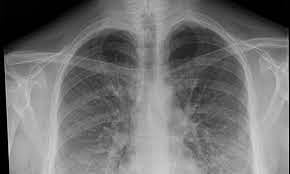

एक्स-रे, सिटी स्कॅन आणि सीबीसी चाचणी (पांढर्‍या पेशींची चाचणी) करून घ्यावी.

पिंपरी, पुढारी वृत्तसेवा: शहरात सध्या न्यूमोनियाची साथ नियंत्रणात आली आहे. कोरोनाच्या काळात गतवर्षी रुग्णालयांमध्ये दररोज 15 ते 20 न्यूमोनियाचे रुग्ण आढळत होते. तर, सध्या हे प्रमाण केवळ दररोज 2 ते 3 रुग्णांवर आले आहे. शहरातील सरकारी व खासगी रुग्णालयांतील ही स्थिती आहे. कोरोना काळात वाढली रुग्ण शहरामध्ये कोरोना काळात म्हणजे 2021 मध्ये एका खासगी रुग्णालयात न्यूमोनियाचे दररोज 15 ते 20 रुग्ण आढळत होते. त्यापेक्षा जास्त प्रमाणात सरकारी रुग्णालयांमध्ये त्याची संख्या वाढली होती.

मात्र, सध्या हे चित्र बरेच बदलले आहे. गेल्या एक ते दीड महिन्यापूर्वी यशवंतराव चव्हाण स्मृती रुग्णालयात न्यूमोनियाचे दिवसाला सरासरी 15 ते 20 रुग्ण आढळत होते. तर, सध्या दिवसाला केवळ 2 ते 3 रुग्ण आढळत आहेत. याबाबत काही खासगी रुग्णालयांमध्ये विचारणा केली असता त्यांच्याकडे एक ते दीड महिन्यापूर्वी दिवसाला 5 ते 6 न्यूमोनियाचे रुग्ण आढळत होते. सध्या दिवसाला केवळ 1 ते 2 रुग्ण आढळत आहे.